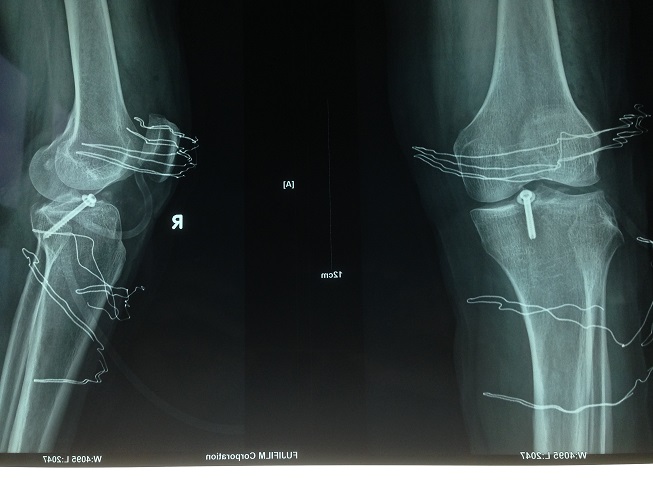

术后患者DR片